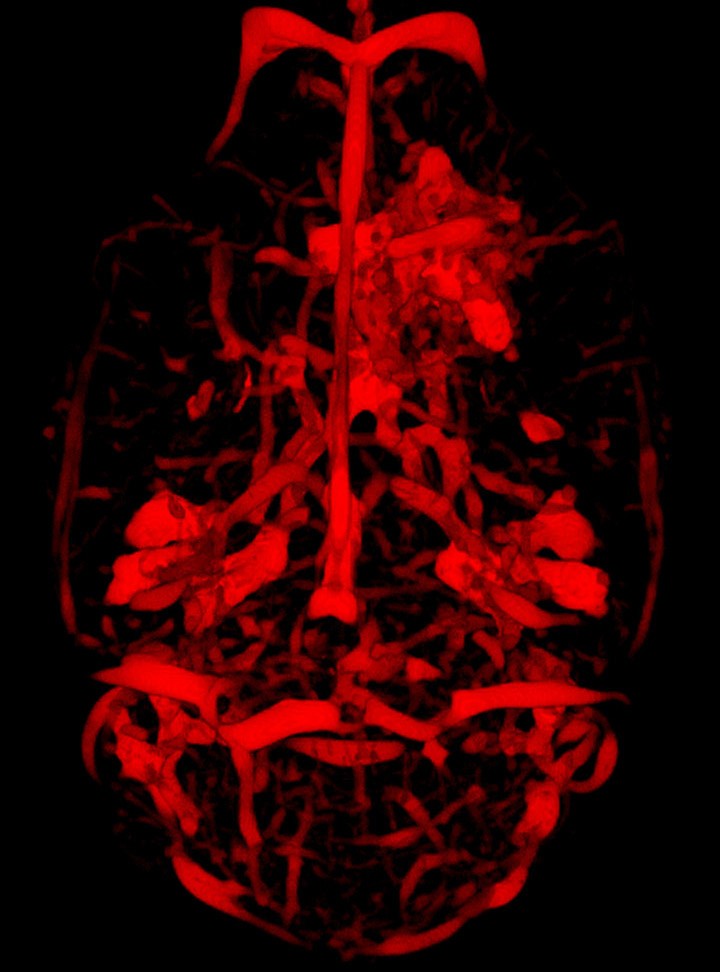

Panique écarlate

Julie Constanzo, Martin Lepage et Benoit Paquette de la Faculté de médecine et des sciences de la santé nous révèlent des vaisseaux sanguins en panique! «Sur cette imagerie par résonance magnétique (IRM), on aperçoit le réseau sanguin d’un cerveau de rat, vu du dessus. La région plus dense, en haut à droite, initialement saine, a été ciblée par radiothérapie. Le but était de reproduire les effets secondaires de ce traitement. En effet, si cette technique d’irradiation entraîne la nécrose (mort) des tumeurs, elle endommage parfois les tissus cérébraux environnants. Dans une sorte de réaction de «panique», des vaisseaux sanguins se mettent alors à croître de façon anarchique. Grâce à la présente méthode d’utilisation innovante de l’IRM, il serait désormais possible pour les cliniciens de suivre efficacement  l’évolution de ces changements vasculaires. Le cas échéant, les patients pourraient bénéficier de l’administration précoce de médicaments appropriés.»